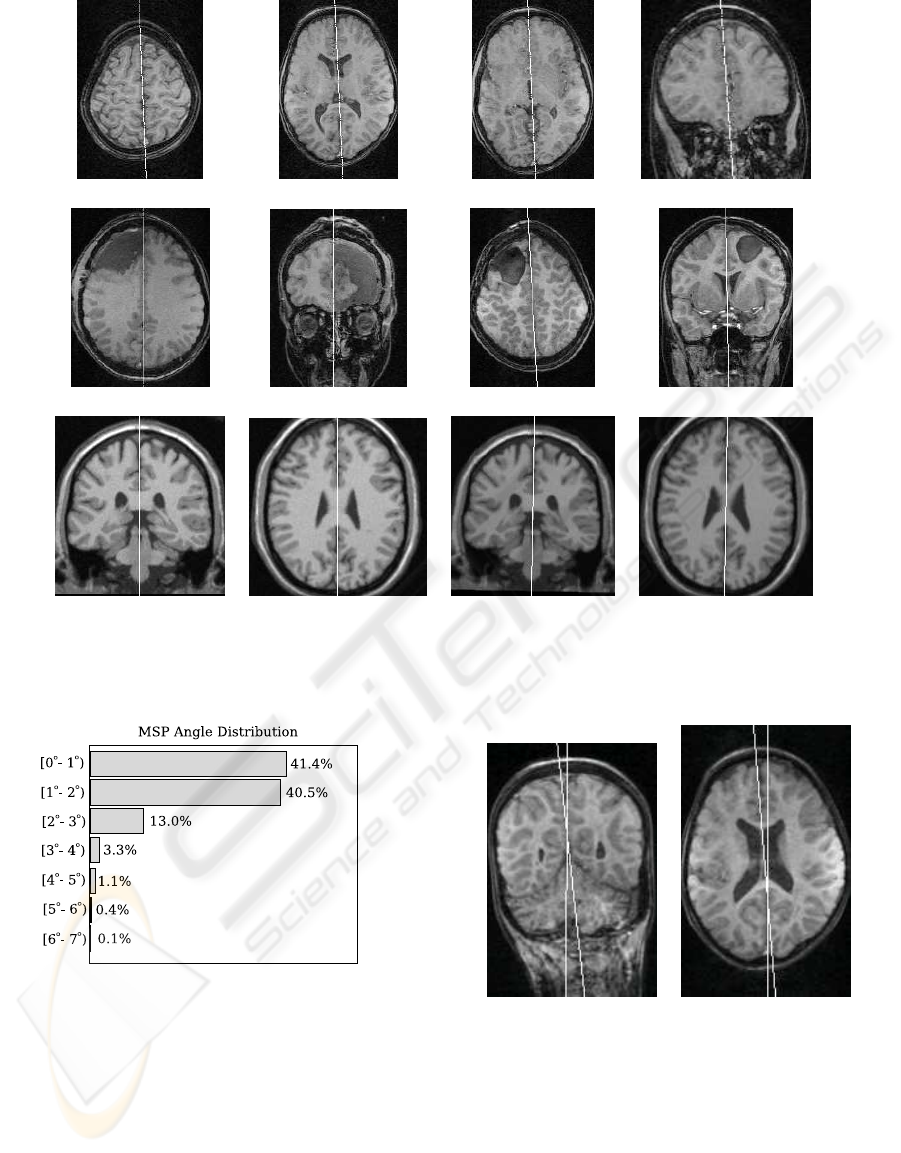

FAST AND ROBUST MID-SAGITTAL PLANE LOCATION IN 3D MR IMAGES OF THE BRAIN